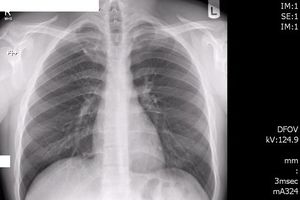

Diagnostic radiology, the imaging modalities using ionizing radiation, produces images of anatomical internal structures of human organs and physiological (functional) biological systems and helps significantly improve patient management and care in screening and diagnosis, assessing treatment response, predicting prognosis, and detecting disease recurrence. Modern diagnostic radiology assures faster, more precise diagnosis and enables monitoring of a large proportion of diseases. It has been estimated that in about one half of all cases, radiological procedures (conventional radiography, fluoroscopy, computed tomography) have a substantial impact on the speed of diagnosis and in a large fraction of cases they are of decisive importance in guiding patient management and therapy.

In diagnostic radiology, x rays, produced by machines, are transmitted through the patient’s body and detected by a receptor (or detection) system to generate the required image of the organs under investigation. The differential absorption of x rays in tissues and organs, owing to their atomic composition, is the basis for the various imaging methods used in diagnostic radiology. Modern diagnostic radiology uses a digital process for image acquisition, transfer, process and storage. Over the past years, with the tremendous technological progress and collaborative efforts in radiation protection, the radiation doses used in diagnostic radiology have been significantly reduced and continue to be reduced through technological innovations especially in CT (ICRP Publication 135 Diagnostic Reference Levels in Medical Imaging; ICRP Publication 121 Radiological Protection in Paediatric Diagnostic and Interventional Radiology; ICRP Publication 105 Radiological Protection in Medicine; ICRP Publication 93 Managing Patient Dose in Digital Radiology).

Diagnostic radiology are mainly applied in the areas: (1) Digital general radiology (DR); (2) Mammography; (3) Fluoroscopy systems; (4) Mobile radiography and fluoroscopy; (5) Bone density scan (DXA); (6) Computed tomography (CT); (7) Conventional tomography and tomosynthesis; (8) Dental radiography / CBCT; (9) Nuclear medicine including hybrid imaging (SPECT/CT, PET/CT, PET/MRI); (10) Cardiology; (11) Neuroradiology; and (12) Paediatrics.

Nuclear medicine uses radioactive substances, called radiopharmaceuticals, in the diagnosis and treatment of a range of diseases. These substances are chosen or especially developed to be taken up predominantly by one organ or one type of cell in the body. Nuclear medicine offers unique diagnostic information in oncology, cardiology, endocrinology, neurology, nephrology, urology and other areas. Such information is not obtainable, or obtainable only with less accuracy, by other modalities. For nuclear medicine diagnostic procedures, trace amounts of radiopharmaceuticals are administered to patients through injection into veins (intravenous), skin (intradermal) or tissues (intraparenchymal) as well as breathing in (inhalation) or eating/drinking (ingestion). After intake, the function, or physiology, of various tissues, organs or organ systems can be demonstrated. For example, in cancer patients, nuclear medicine imaging can be used for diagnosis (i.e. is a cancer present), staging (i.e. how far has it spread), assessment of response to therapy or of possible disease recurrence. Nuclear medicine cameras are now commonly combined with a CT unit (e.g. hybrid SPECT/CT and PET/CT) which allows precise anatomic localisation of pathology. (Figure 1, Figure 2a, 2b)